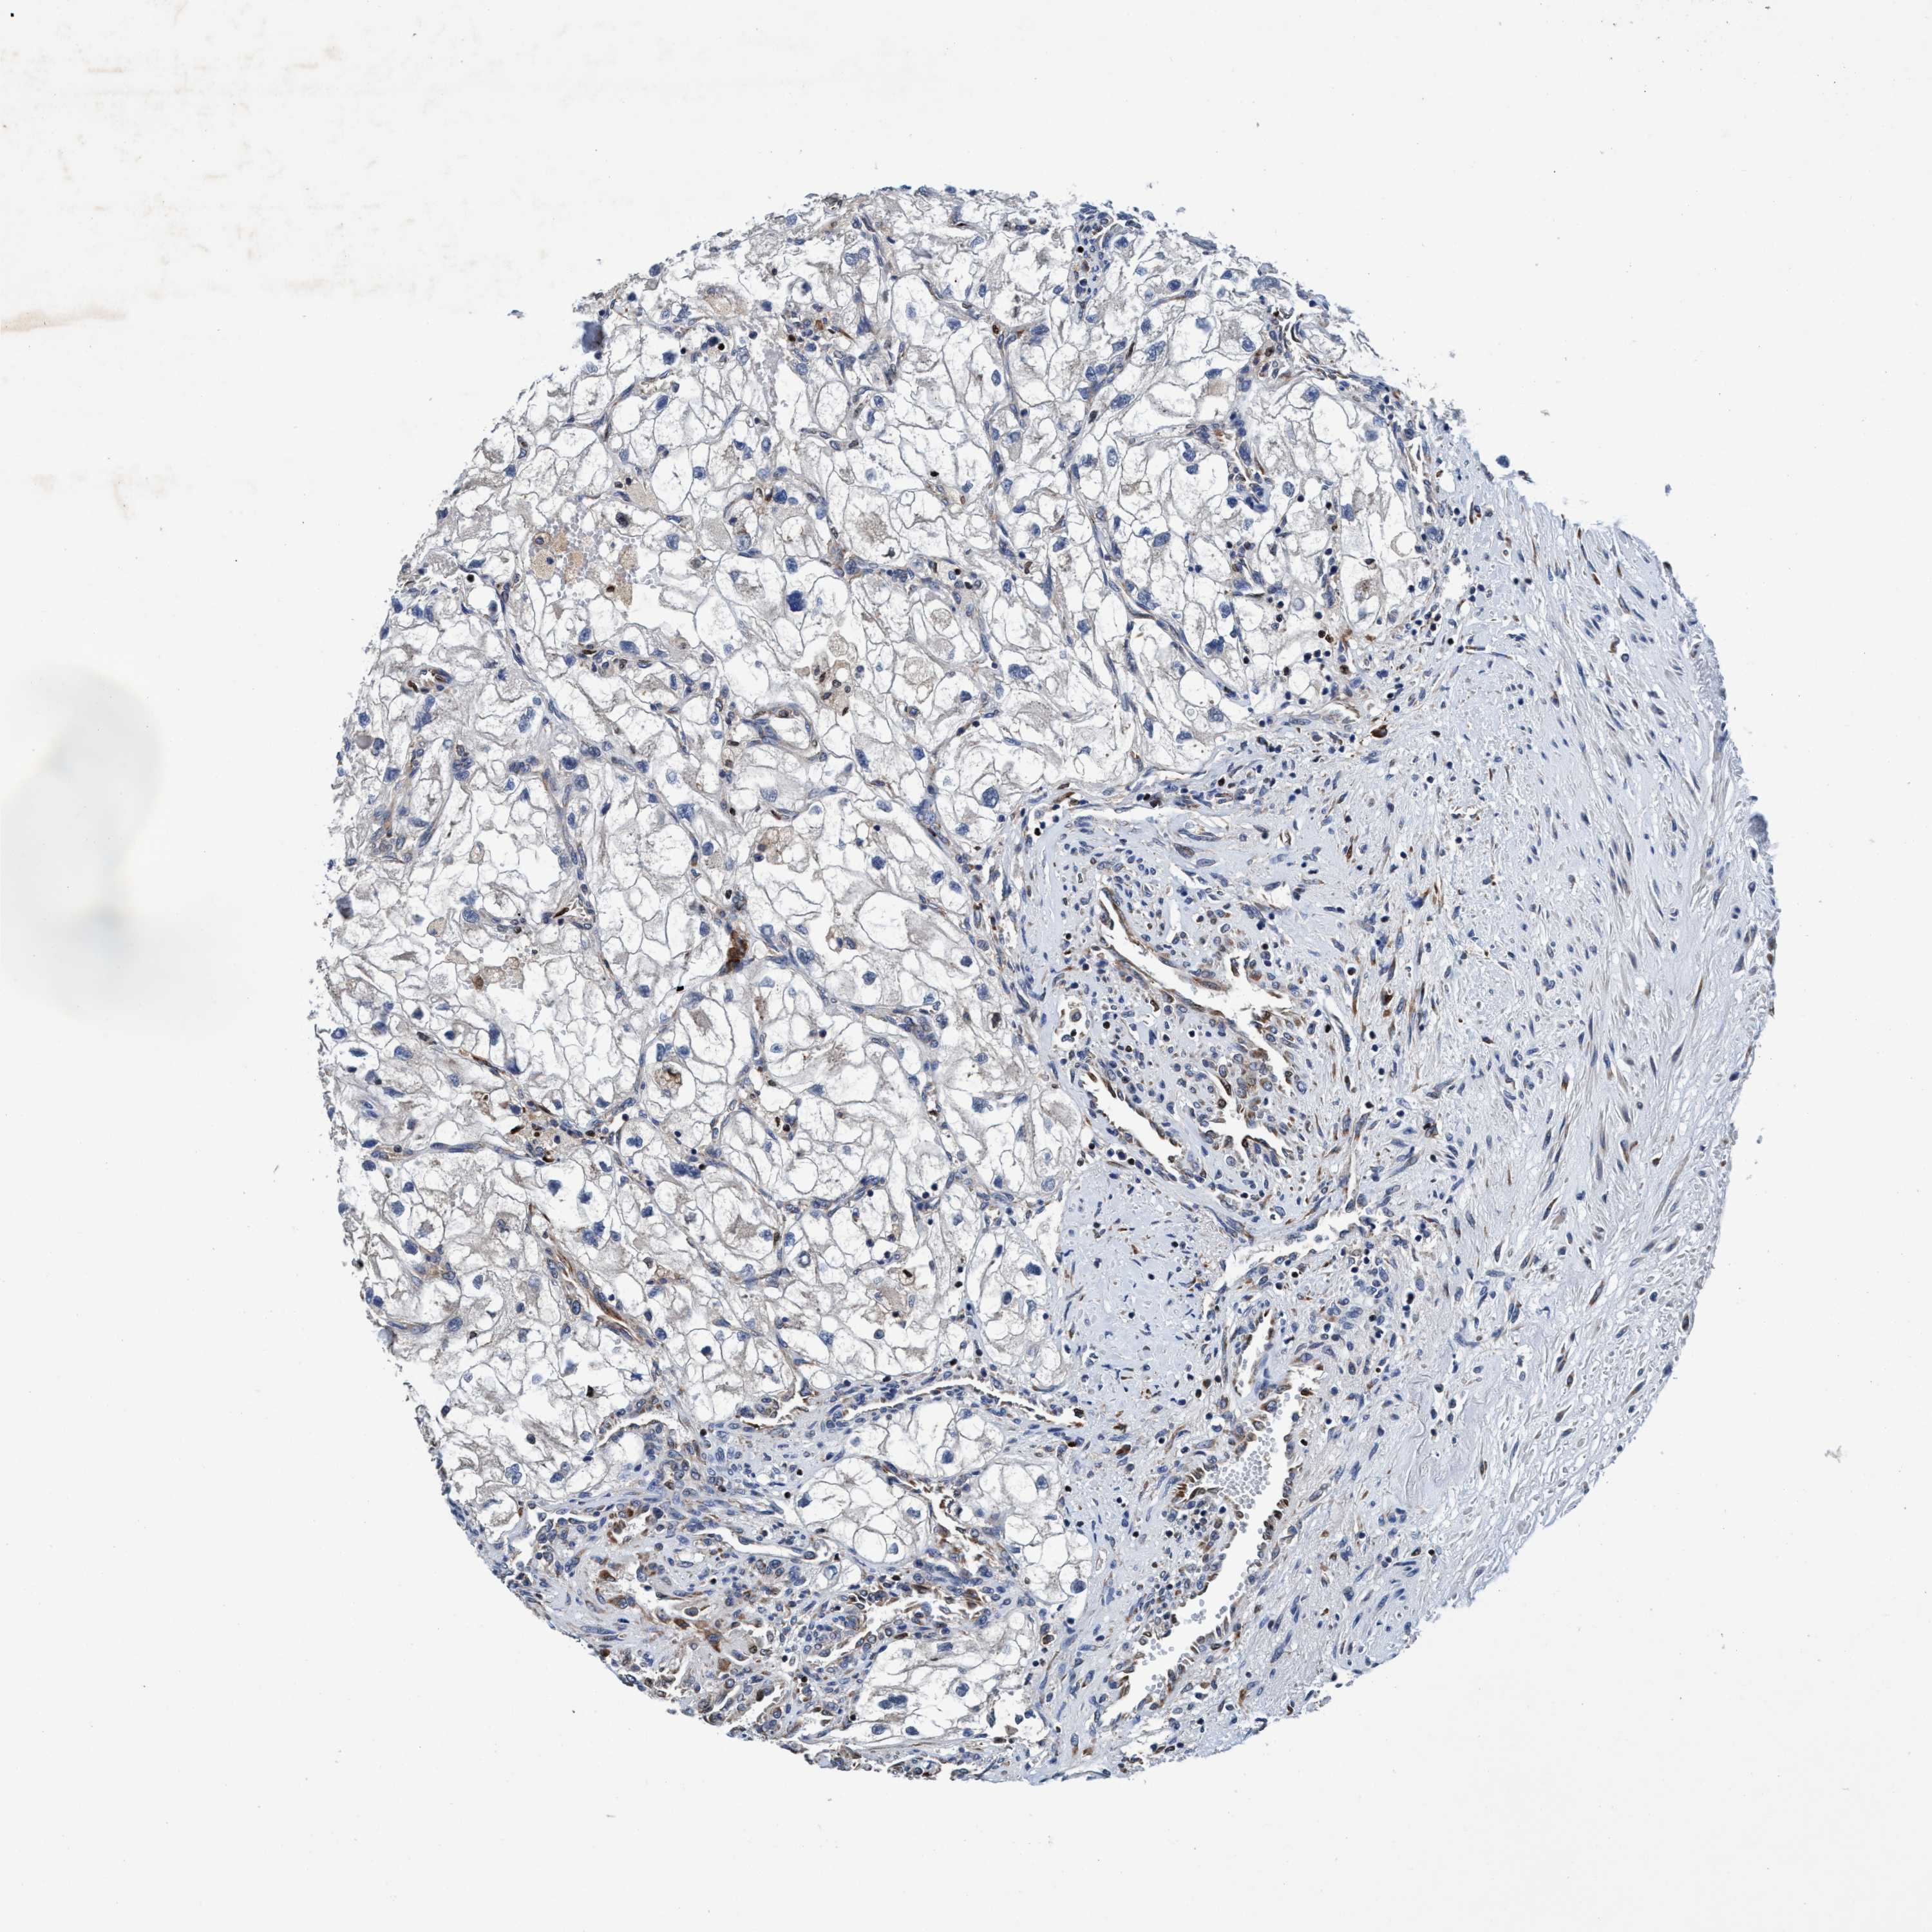

CANCER RENAL CANCER Show tissue menu

KICH TCGA KIRC TCGA KIRC VALIDATION KIRP TCGA PROTEIN RCC CPTAC PROTEIN EXPRESSION

KIDNEY CHROMOPHOBE (TCGA) - Interactive survival scatter ploti

ENDOG is not prognostic in Kidney Chromophobe (TCGA)